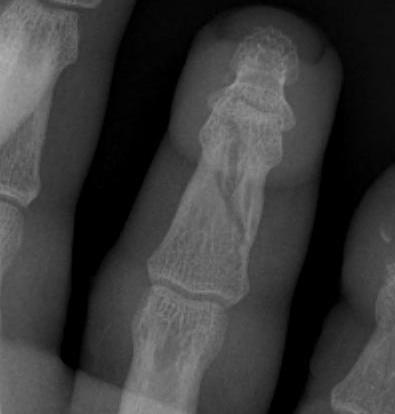

Condylar fractures of head of P1 / P2

Mechanism

- torsional and valgus impaction

London classification

Type 1 Unicondylar, undisplaced

Type 2 Unicondylar, displaced

Type 3 Bicondylar

Displaced unicondylar

- percutaneous K wire

- ORIF with screw

![]()

Open reduction

- P1 – between central slip and lateral band

- P2 – lateral to terminal extensor tendon

- must preserve collateral ligament which supplies blood

Type III bicondylar fractures

- difficult fractures

- 90 degree condylar plate

- lag screw and plate

- high risk of joint stiffness